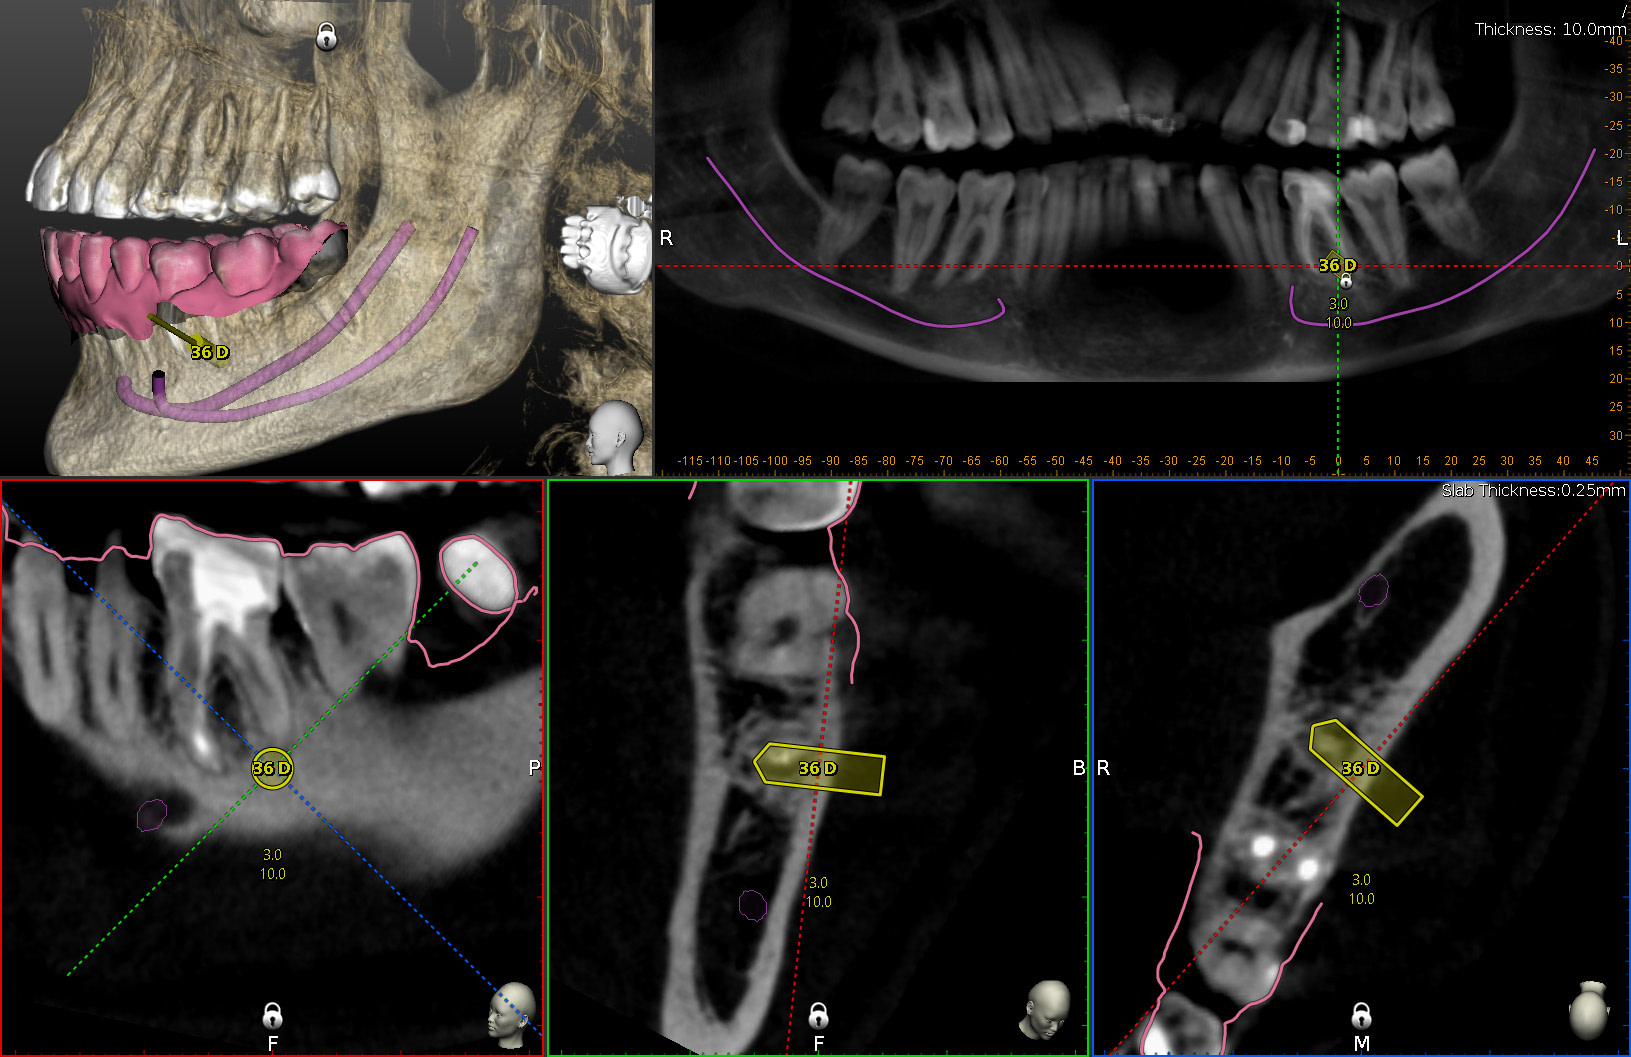

The second case was an apicectomy of lower molar 36 distal root. This would normally be a very difficult procedure to do due to poor visibility, difficulty to visualise the 3D position of the root apex. However this procedure was completed with high accuracy and efficiency.

The Surgical Process

Surgical Planning

CBCT and intraoral scans are aligned together. Planned to use trephine drill to create window through cortical bone as well as remove the 36D root tip. Axis and depth of the osteotomy are designed with the included planning software.

Live Navigation During Surgery

Live navigation of trephine drill. I had to alter the axis slightly due to difficult access. However the tip of the drill reached the planned location and depth.